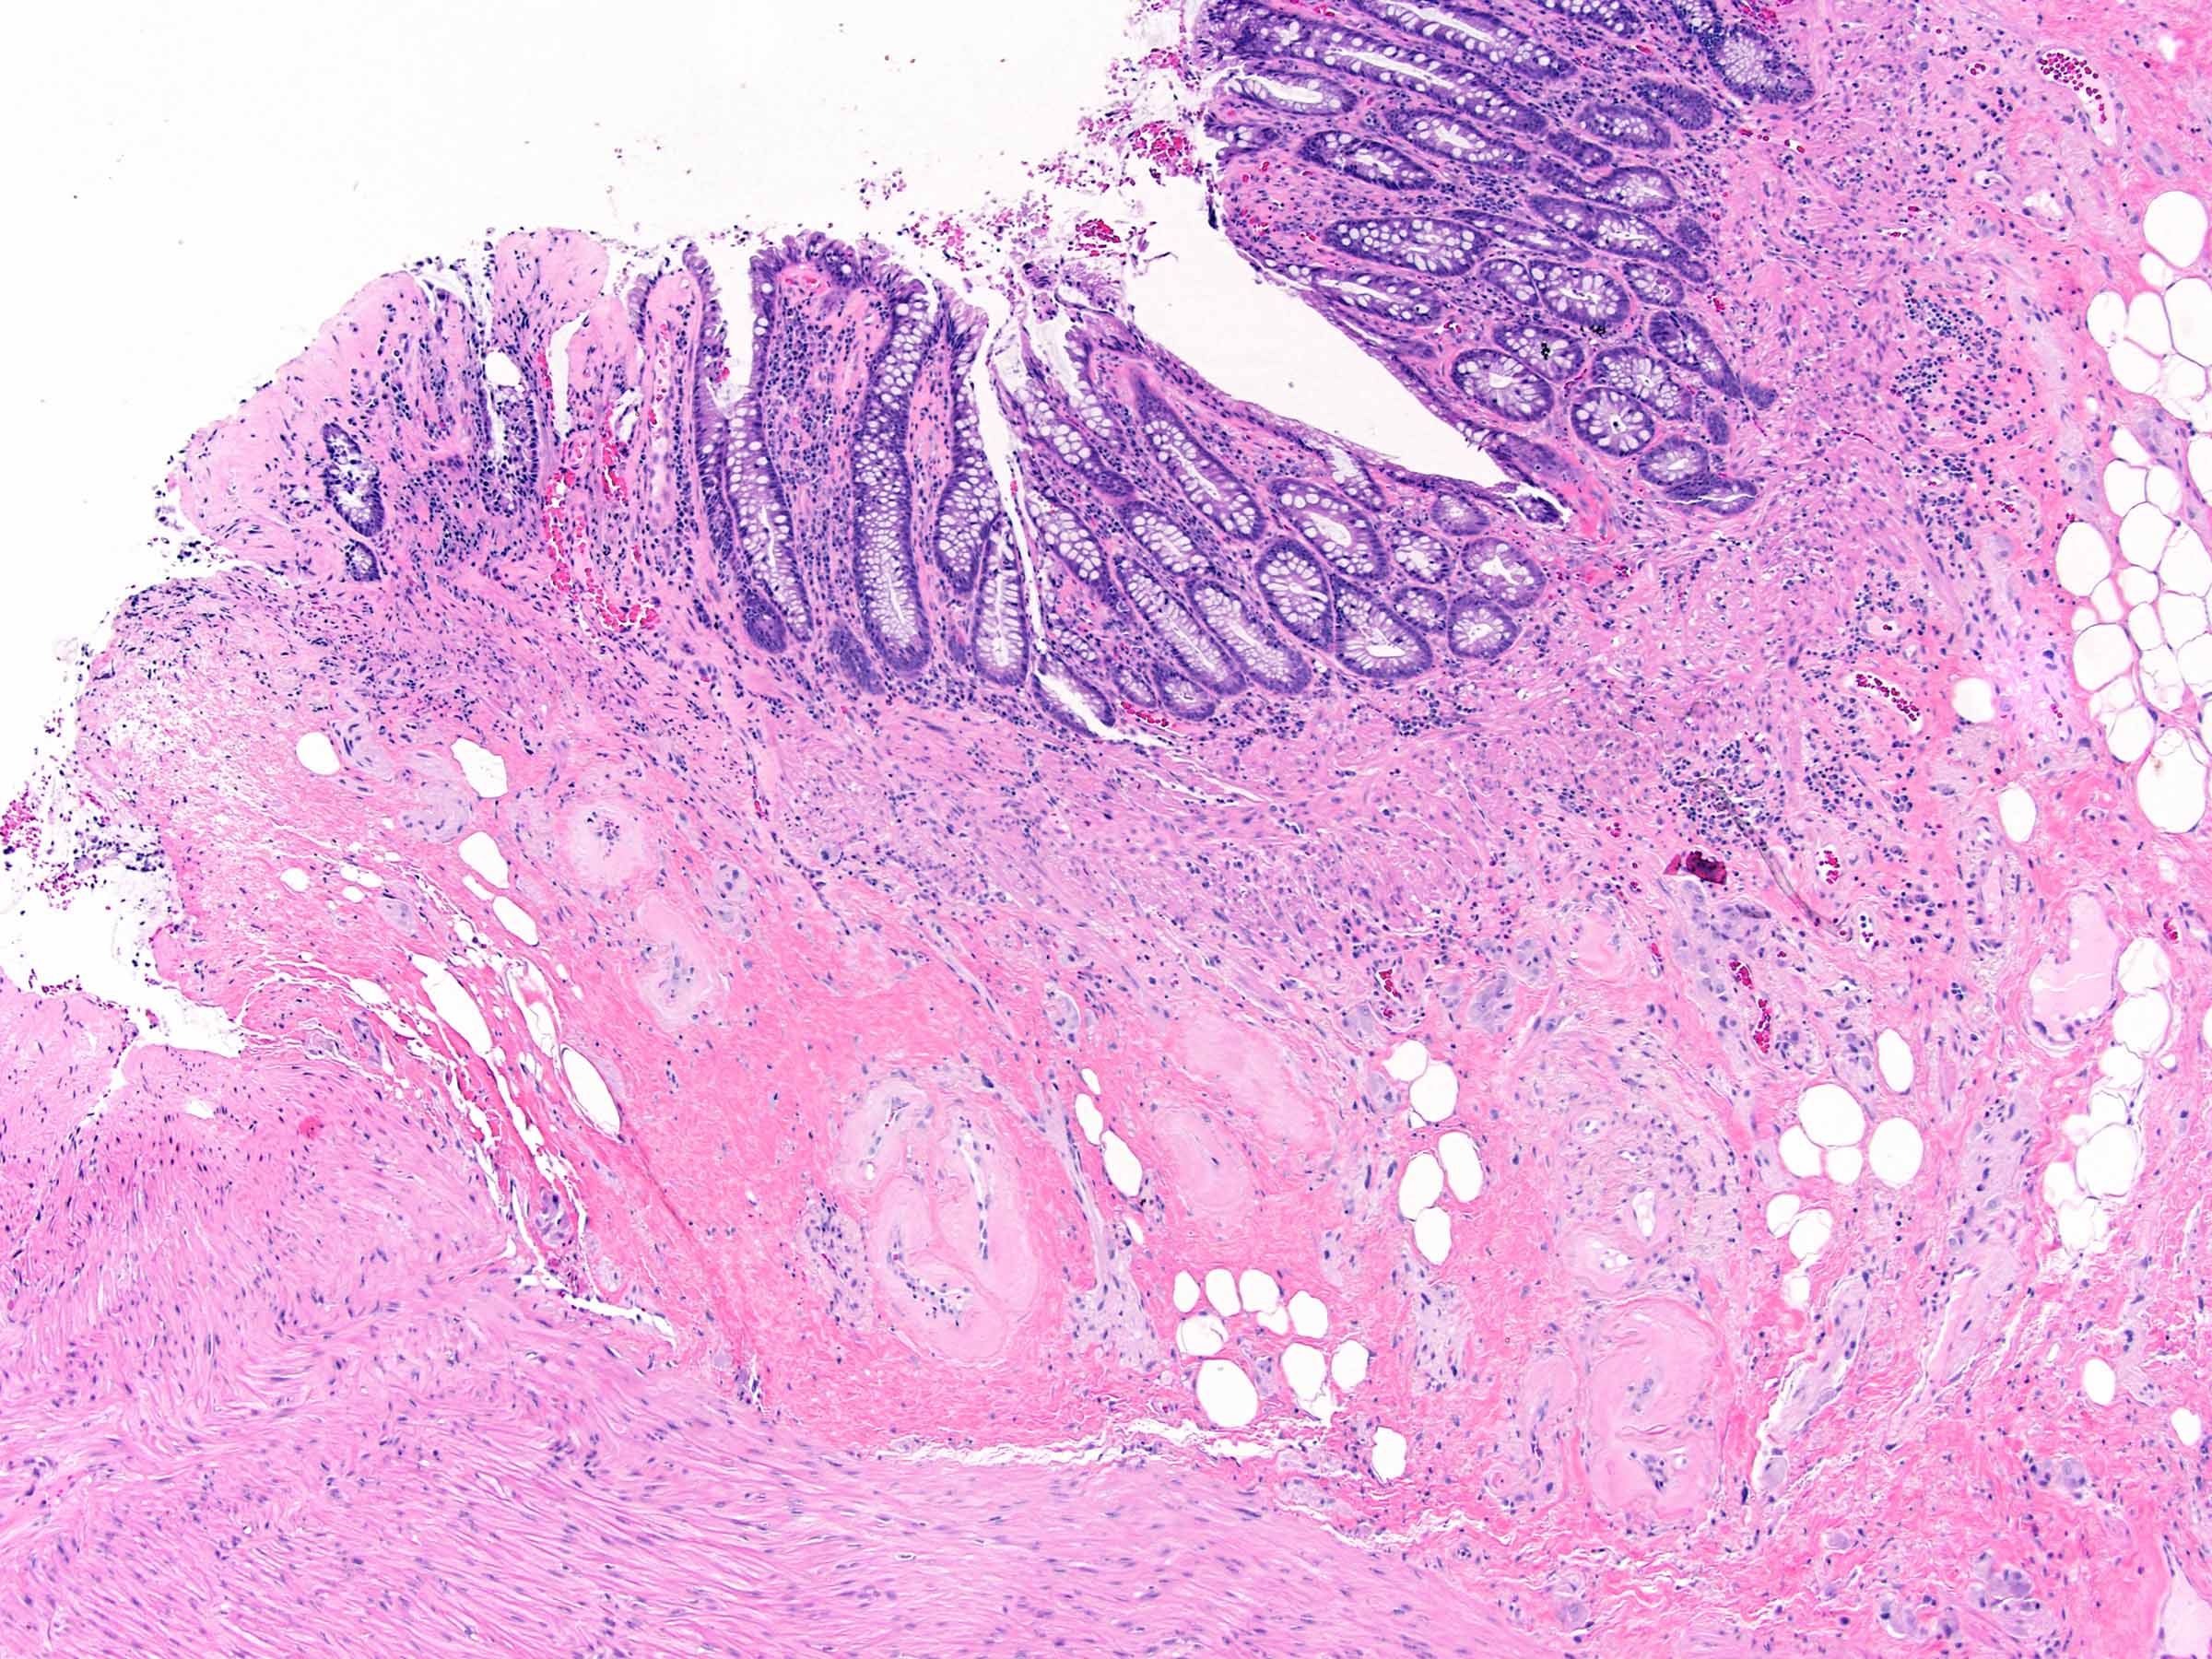

Microscopic (histologic) images

- Chronic radiation colitis (> 6 months after radiation treatment):

- Submucosa and deeper layers:

- Vasculature

- Hyalinization and fibrosis of vessel wall

- Intimal thickening

- Vascular ectasia or narrowing

- Thrombosis

- Endothelial cell atypia

- Vasculature

E. Radiation colitis, chronic. Chronic radiation colitis is expected at > 6 months postradiation therapy. Sections show ulcerations, mild epithelial atypia, architectural changes and atrophy. The lamina propria contains fibrosis, mild chronic inflammation and fibroblast atypia (enlarged hyperchromatic nuclei). The vasculature within submucosal and deeper layers contains hyalinization of vessel wall and intimal thickening. Vascular ectasia, narrowing and thrombosis can also be present. Collagenous colitis (answer A) typically presents with history of watery diarrhea and a > 10 μM subepithelial collagen table (collagenous band). Infection (bacterial) (answer B) will present with an acute clinical history (example: diarrhea and vomiting) after an inciting event (example: food consumption, travel). Acute colitis and granulomas can sometimes be seen. Viral infections (example: cytomegalovirus, Epstein-Barr virus) can occur in immunocompromised patients (example: HIV or transplant) and will contain atypical cells with nuclear changes. Mucosal prolapse (answer C) can present endoscopically as a polyp and contains ingrowth of thick muscle bundles that can mechanically squeeze ensnared epithelium. This is accompanied by variable inflammation, ulceration and reaction epithelial change. Acute radiation colitis (answer D) is expected at < 6 months postradiation therapy. The inflammation is typically eosinophilic (characteristic) with eosinophilic cryptitis, crypt abscesses and lamina propria eosinophilia. Sections demonstrate reduced mitotic activity, apoptosis, reduced goblet cell mucin, goblet cell swelling, degenerative changes and atypia (nuclear enlargement and malorientation).